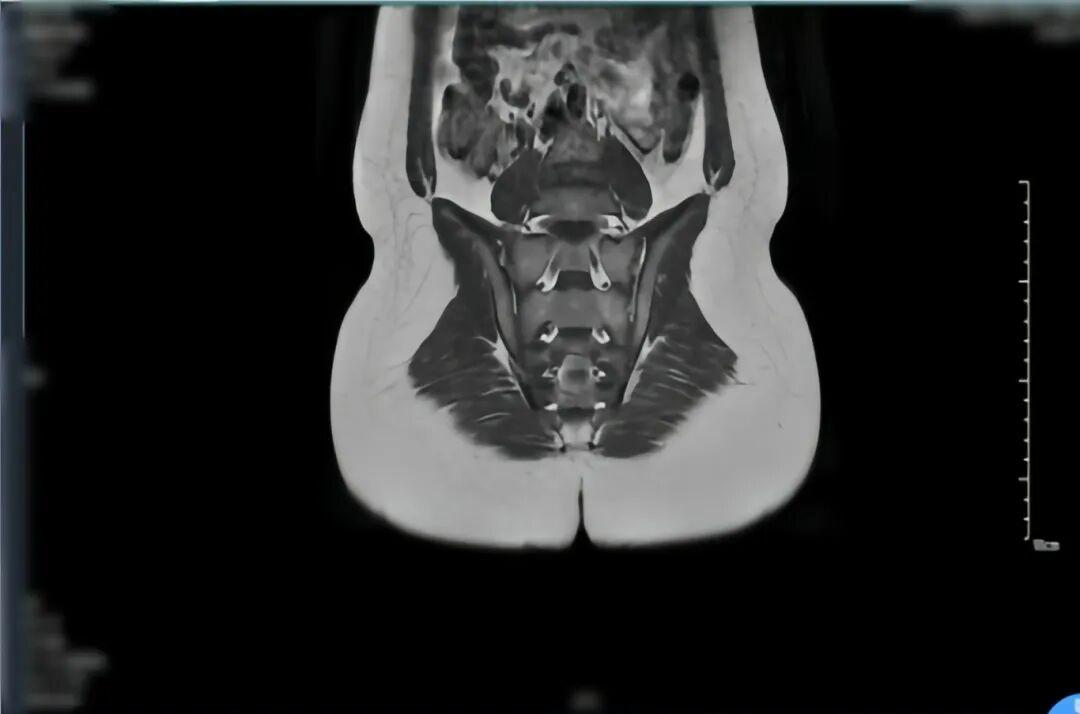

检查结果显示,小轩的血沉、C-反应蛋白等炎症指标明显升高,HLA-B27 筛查呈阳性(该指标与脊柱关节病密切相关,对诊断有重要参考价值);右足磁共振检查发现距骨、跟骨存在“骨髓水肿”,骶髂关节影像也显示关节面有骨髓水肿和炎症迹象。

结合小轩的年龄、症状及检查结果,最终明确诊断为幼年特发性关节炎(JIA)。这是一种儿童期常见的自身免疫性疾病,简单来说,就是免疫系统“敌我不分”,错误地攻击了自身关节,引发慢性炎症和疼痛。